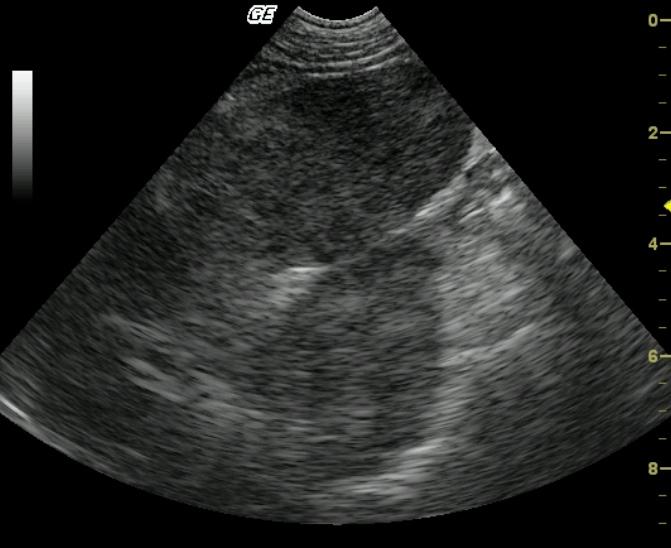

A 10 year old MN Pug was presented for the evaluation of anorexia, vomiting, diarrhea, and pollakuria. No abnormalities were noted on the physical exam. The CBC showed a neutrophilia, monocytosis, and thrombocytopenia. A serum biochemical profile revealed elevated serum alkaline phosphatase, elevated ALT, elevated AST, elevated GGT enzyme activities as well as hypercholesterolemia.